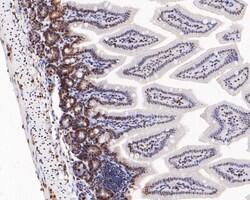

Invitrogen™ Phospho-ATF2 (Thr71) Recombinant Rabbit Monoclonal Antibody (SC05-90)

The transcription factor ATF-2 (also called CRE-BP1) binds to both AP-1 and CRE DNA response elements and is a member of the ATF/CREB family of leucine zipper proteins. ATF-2 interacts with a variety of viral oncoproteins and cellular tumor suppressors and is a target of the SAPK/JNK and p38 MAP kinase signaling pathways. Various forms of cellular stress, including genotoxic agents, inflammatory cytokines and UV irradiation, stimulate the transcriptional activity of ATF-2. Cellular stress activates ATF-2 by phosphorylation of Thr69 and Thr71. Both SAPK and p38 MAPK have been shown to phosphorylate ATF-2 at these sites in vitro and in cells transfected with ATF-2.

| Immunohistochemistry (Paraffin), Western Blot, Immunocytochemistry | |